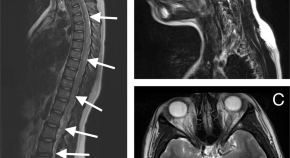

Spinal cord ischaemia is a rare complication following the gluteal injection of Benzathine benzylpenicillin. The hypothesis is embolization of the Penicillin products retrogradely through the Superior gluteal artery and cause occlusion of the vasculature that supply the spinal cord. This article includes literature review of the hypothesis behind the Spinal cord ischaemia and highlights the previous cases reported.